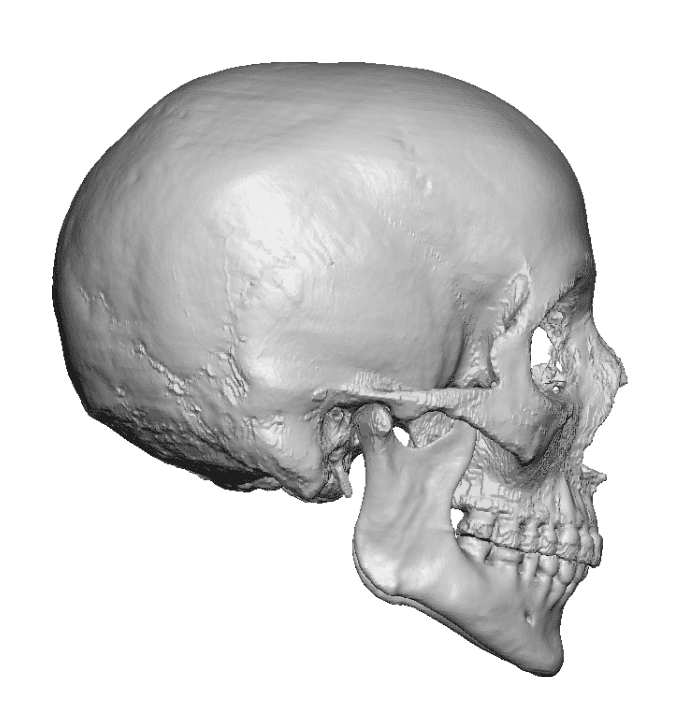

Severe narrowing skull deformity from prior sagittal craniosynostosis repair as an adult.

Complete replacement of entire skull by a custom implant with temporal fat injections.

Severe narrowing skull deformity from prior sagittal craniosynostosis repair as an adult.

Complete replacement of entire skull by a custom implant with temporal fat injections.